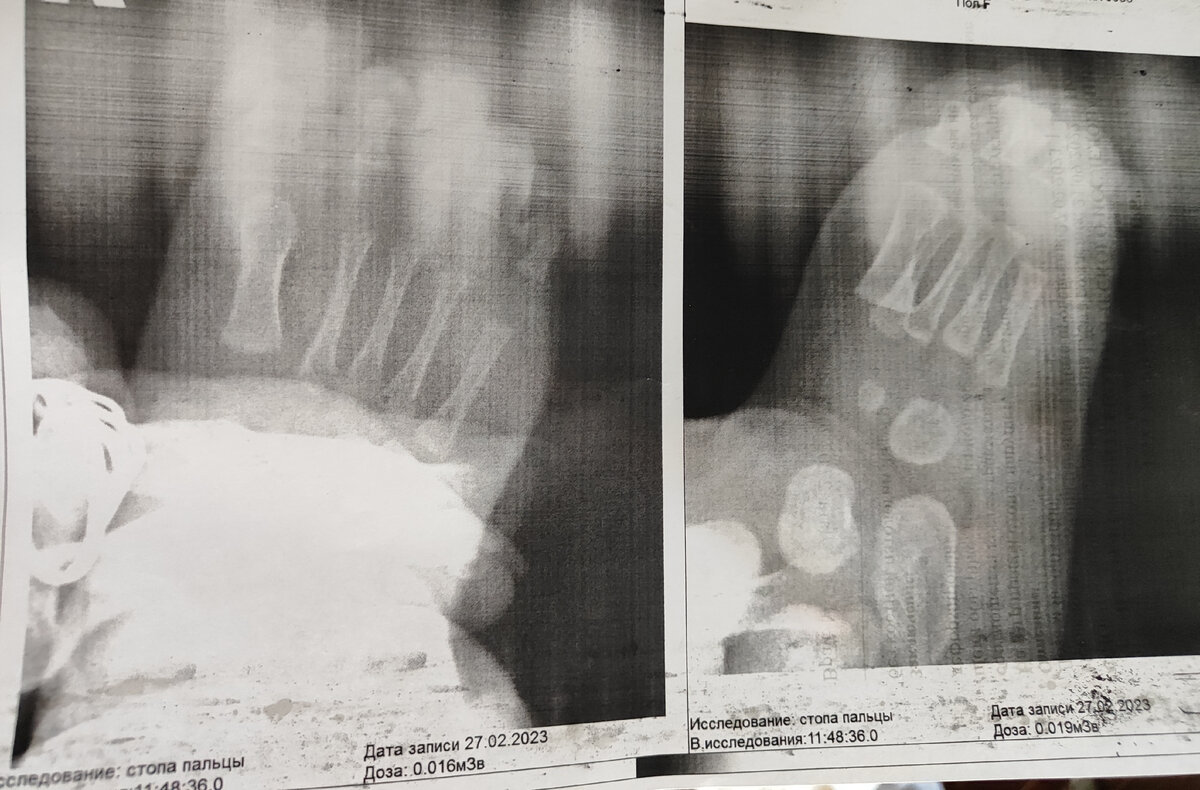

Тут на снимке ещё моя рука, я придерживаю ножку

Я не стала спорить, звонить в страховую, потому что на такие мероприятия просто не было времени, у нас и так уже был на руках замученный ребенок. Заплатила около 700 рублей за рентген. Врач сказала, что мы сможем с рентгеном второй раз пройти без очереди.

Врач сказала, что дисплазия не тяжелая, что на снимке все не так уж плохо. Достаточно 2 месяца поносить корсет и все придет в норму. Но, она должна жить в этом корсете 24 часа в сутки. Иначе придётся носить 4 месяца потом. Я немного в шоке, так как это получается ребенок 2 месяца не будет развиваться, переворачиваться. Думаю, что все-таки будем совмещать корсет и снимать его периодически. Также назначили массаж, электрофорез, парафинтерапию. Последнего у нас по-моему нет в поселке, ну и массажист платный, конечно.